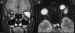

53-02.jpg (9588 bytes)

Figuras 2a, b y c. Retinoblastomas bilaterales calcificados. Imágenes axiales mediante TC (a, b) y secuencia potenciada en T2 de RM. El calcio se define mejor en el estudio de TC.

La resonancia magnética (RM) muestra menor sensibilidad en la detección de calcio que la US o la TC, sin embargo supera a estas dos técnicas en la valoración de extensión local, diseminación al SNC y en el diagnóstico diferencial con entidades que simulan al RTB (1) (figura 2c). El tumor aparece iso o levemente hiperintenso respecto al vítreo en secuencia eco de espín potenciada en T1 (SET1) en relación a hemorragia intratumoral y al depósito de sustancias paramagnéticas asociadas a calcificaciones tumorales (6) (figura 3). En secuencia eco de espín potenciada en T2 (SET2) la señal del tumor es hipointensa respecto al vítreo. El grado de extensión local se valora tras la administración de gadolinio intravenoso mediante secuencias SET1 con saturación de la grasa. Aunque el realce tumoral es variable, siempre ha de realizarse estudio con contraste ya que ayuda a identificar enfermedad retrobulbar (4).

53-03.jpg (12263 bytes)

Figura 3. Secuencia axial potenciada en T2 de retinoblastoma bilateral con hemorragia vítrea asociada en el lado izquierdo.